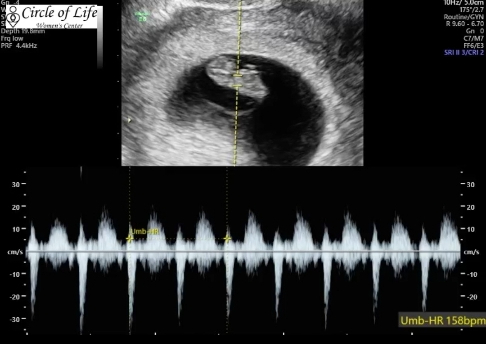

Trent and I attended our first doctor’s appointment on August 1st. The drive to the doctor’s office was rough for me. I was super nauseous by the time we got there (2 hour drive from our house) but I knew we were about to see our baby, and that allowed me to push through the pain to walk into the office. The doctor determined I was just shy of 8 weeks through the ultrasound. We got to see our little baby and hear the perfect sounding heartbeat. The doctor shared that the baby’s heartbeat was “nice and strong” at 158 bpm.